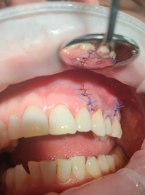

SPECJALISTA RADZI: Nieskuteczna apikotomia wierzchołka korzenia – ponowna resekcja czy powtórne leczenie kanałowe?

Zgłosiła się do mnie 60-letnia pacjentka z nieszczelną i nieestetyczną koroną protetyczną osadzoną na zębie siecznym szczęki. Pacjentka poinformowała, iż ząb był poddany przed laty zabiegowi resekcji. Wykonane zdjęcie potwierdziło wcześniej wykonaną apikotomię oraz obecność niewielkich zmian zapalnych w tkankach okołowierzchołkowych. W kanale stwierdzono dobrze kontrastujący się ćwiek (prawdopodobnie srebrny); w części koronowej kanału był widoczny krótki indywidualny wkład koronowo korzeniowy. Co mogę zasugerować pacjentce? Jakie są możliwości leczenia?